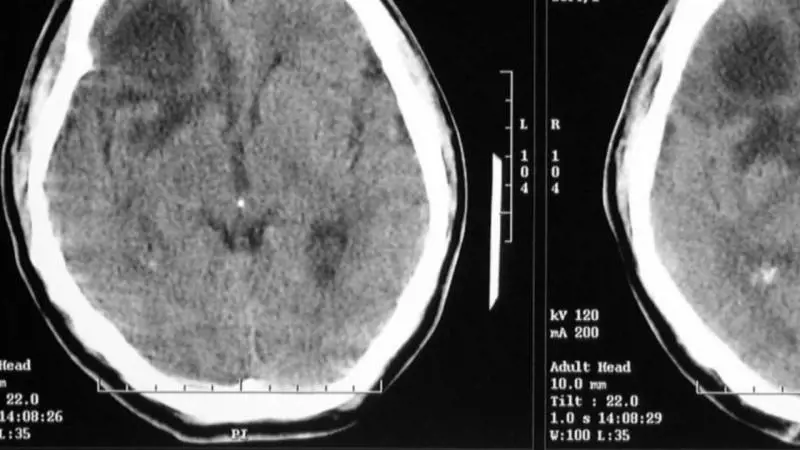

California - Tramite la stimolazione magnetica transcranica (Tms) della corteccia parietale posteriore sinistra del cervello si può "disattivare" la normale pianificazione dei movimenti, inducendo il corpo a trasferire le funzioni della mano destra a quella sinistra. È la scoperta di Flavio Oliveira, dell’Università della California a Berkeley

Lo studio Lo studioso è riuscito a "confondere" quest’area del cervello inducendo dei volontari a fare delle cose con la mano che altrimenti non userebbero di preferenza. L’esperimento è stato pubblicato sulla rivista dell’Accademia Americana delle Scienze "Pnas". L’area scoperta è la corteccia parietale posteriore, già nota perchè importante nella pianificazione dei nostri movimenti.

Da destri a mancini Ma chi decide se usare l’una o l’altra mano? I ricercatori hanno chiesto a un gruppo di volontari destrimani di raggiungere con entrambe le mani degli oggetti in varie posizioni su di un tavolo, poi hanno "disturbato" la corteccia parietale posteriore sinistra e destra con la Tms, tecnica non invasiva e indolore che crea interferenza con le onde elettriche del cervello e "spegne" temporaneamente l’area su cui viene "puntata".

Puntando la Tms sulla corteccia parietale posteriore sinistra, i volontari prendevano a usare di preferenza la mano sinistra piuttosto che la destra. Questa zona della corteccia, dunque, ha un ruolo nella pianificazione sulla mano da usare.